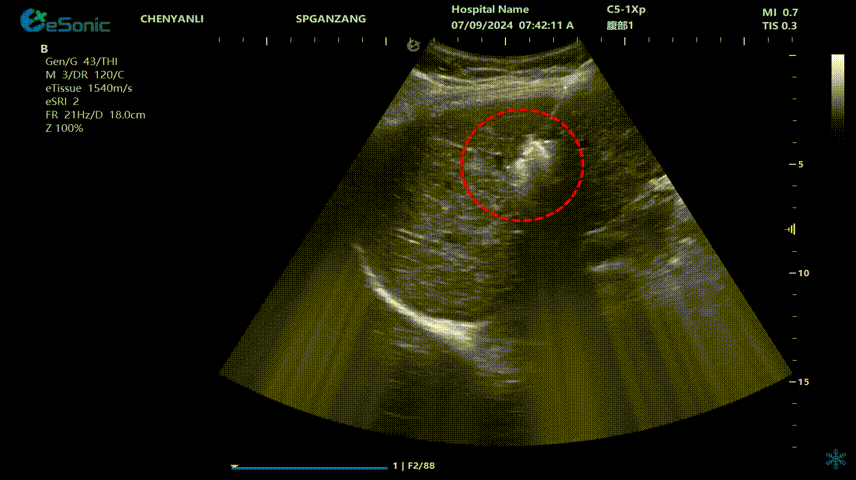

640 (2).gif

肝癌射频消融动态视频

红圈为病灶位置

肝癌射频消融:全麻下彩超探头引导射频针分别植入肝右叶两个稍高回声结节,固定消融,至结节全部为强回声覆盖,覆盖良好,缓缓灼烧针道后退针。